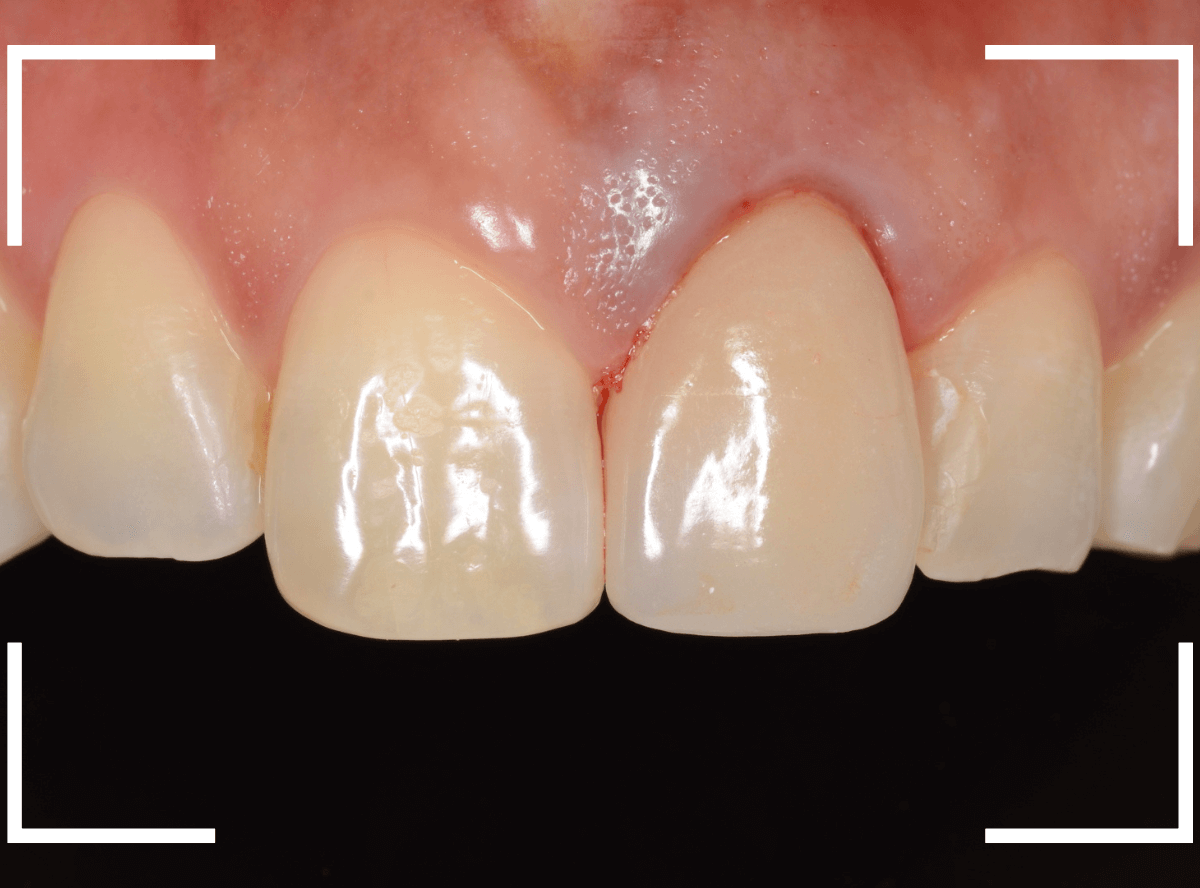

今回は、審美性と、清掃性が高く、歯周病が進行しにくいという利点を考慮して、ジルコニア・セラミックでの治療を選択されました。

ジルコニア・セラミックset後の状態です。

仮歯で細かく調整したおかげで、下の歯のかみ合わせは若干の調整で済む事ができました。

set前との比較です。

歯肉の治療がひと段落したところで、ジルコニア・セラミックで再製しました。

治療前と治療後の比較、前から見たところです。

患者さんにも満足いただけまして、ホッとしました。

裏側の歯肉も綺麗に治りました。

セラミックの表面はつるつるしていますので、歯周病の原因になるプラークがたまりづらく、治療後の経過も期待できます。